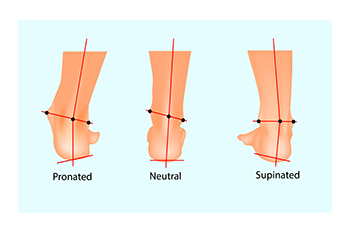

The Dangers of Excessive Supination

Supination, or underpronation, occurs when your body weight shifts to the outer edges of your feet during walking or running. In a normal stride, your foot should gently roll inward, or pronate, distributing your weight evenly across the ball of the foot, and pushing off using the big toe. In supination, most of the weight is on the outer edge, with push-off from the outer toes. These faulty foot mechanics can have significant implications for overall health. Excessive supination can lead to issues such as back and hip pain, knee stress, ankle injuries, and heel pain. The abnormal weight distribution also increases the risk of chronic pain and injuries, and makes you more susceptible to ankle problems and other foot conditions. Supination can result from inherited structural problems in the foot, like high arches. Weakness in the muscles of the foot, ankle, and leg can also contribute. Footwear that lacks sufficient support, body misalignment, or prior foot injuries that have damaged tendons or muscles can also be factors. To address problems caused by excessive supination, it is suggested that you make an appointment with a podiatrist who can diagnose your structural foot problems, perform a gait analysis, and provide appropriate treatment options.

Biomechanics in Podiatry

Podiatric biomechanics is a particular sector of specialty podiatry with licensed practitioners who are trained to diagnose and treat conditions affecting the foot, ankle and lower leg. Biomechanics deals with the forces that act against the body, causing an interference with the biological structures. It focuses on the movement of the ankle, the foot and the forces that interact with them.